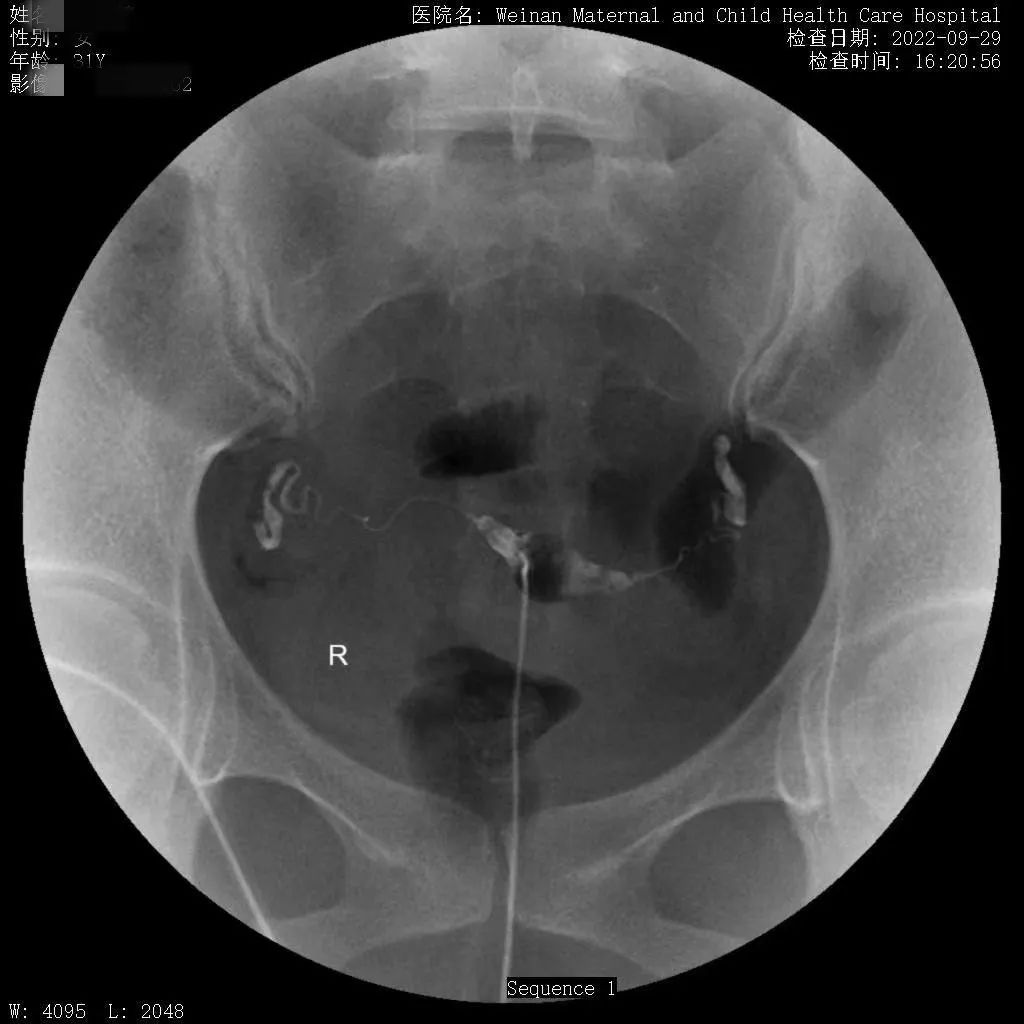

为满足临床需求,除开展传统X线检查外,近年又相继开展了静脉肾盂造影、“T”型管造影及子宫输卵管造影等多种造影检查、乳腺钼靶成像、遥控灌肠治疗小儿肠套叠等较前沿的X线检查。尤其是治疗小儿肠套叠,现已治愈几百余例患儿,遥控灌肠整复仪治疗小儿肠套叠具有安全、迅速、高效的特点,避免了患儿手术,减轻了家庭经济负担。

不育不孕症的子宫输卵管造影检查